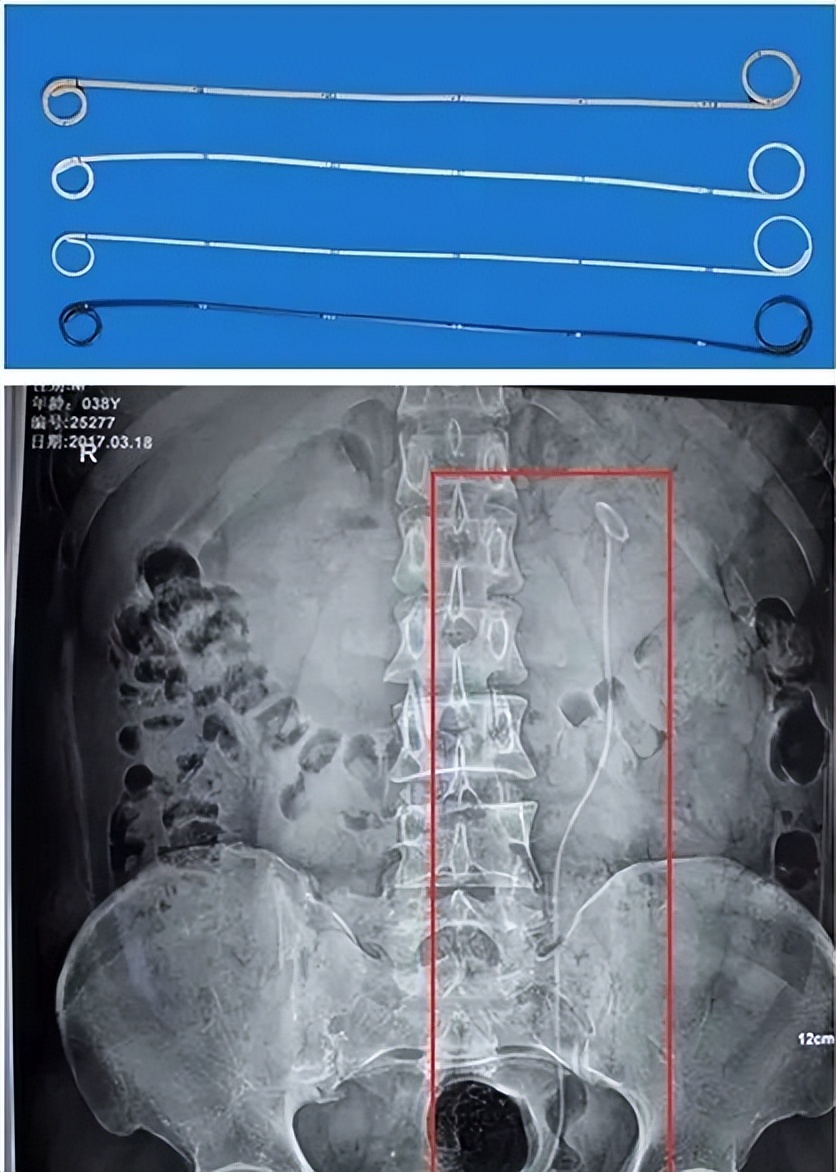

双J管(Double J Ureteral Catheter)是一条中空的细软管,两端为J型构造,因此而得名。

图片来源:网络,侵权请联系删除

泌尿结石手术后,为解除输尿管术后炎性水肿和碎石排出造成的暂时性梗阻,防止术后伤口漏尿和输尿管狭窄,往往会将“双J管”的一端挂悬于患者肾盂,另一端盘旋在患者膀胱,以此替输尿管作暂时性的支撑和引流,保证尿流可以不受干扰地从肾脏流通到膀胱。一般而言,“双J管”的置入,也象征着手术已经打通输尿管阻塞,肾积水开始消除。

最后患者出现严重的腰痛,来院将这条“潜伏”6年的双J管取出后发现,不仅双J管已经出现了断裂,管壁上还布满了结石,对患者身心健康造成了巨大的伤害。